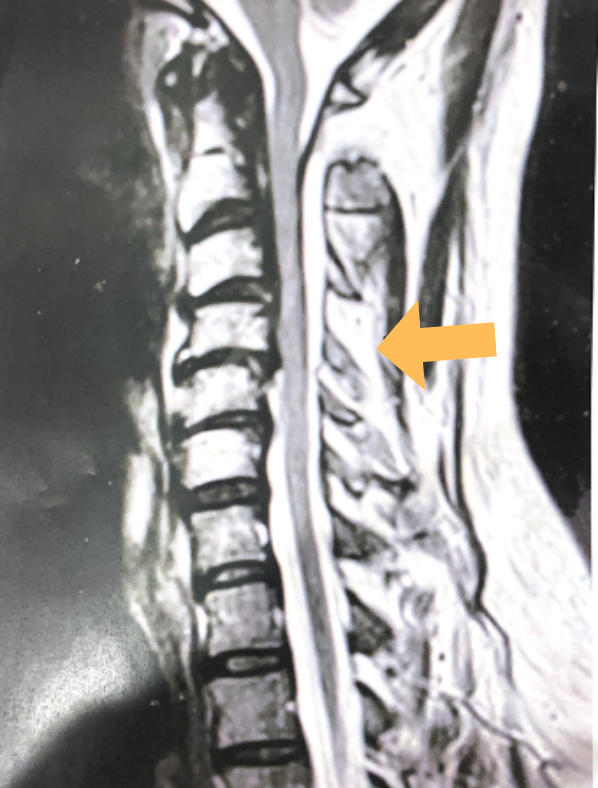

Fig 2. MRI of thoracic spine showing syringomyelia.